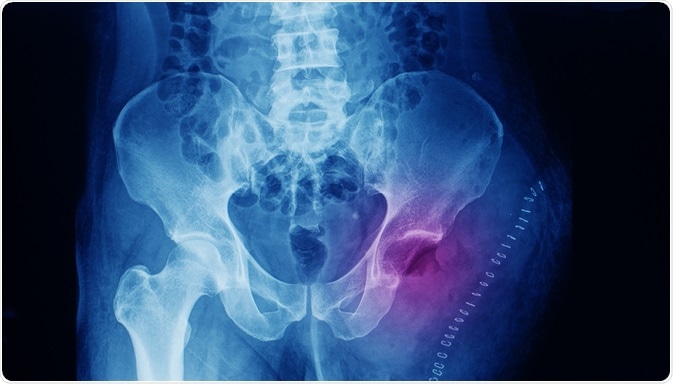

Pelvis x-ray of a patient that has osteosarcoma at the thigh. The patient underwent left side hip disarticulation and wide excision of the tumor. Image Credit:  Yok_onepiece / Shutterstock

X-ray imaging reveals that the tumor is solid, hard, and irregular, with an appearance similar to a fir-tree or as if it has been moth-eaten. This distinctive look is likely due to the calcified bone radiating at right angles in the tumor spicules known as Codman’s triangle.